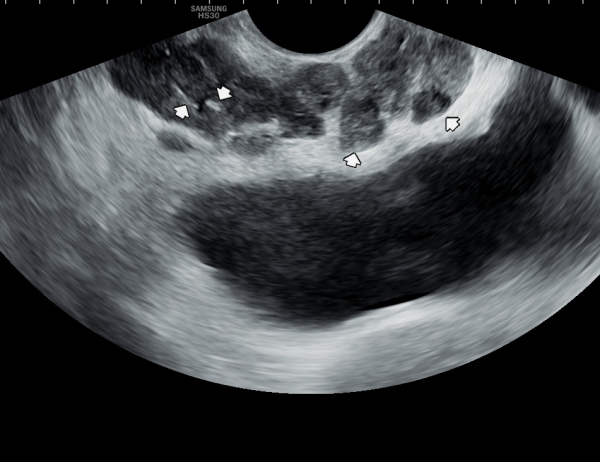

사정관의 입구가 좁아져 정낭과 정관등의 순환 장애로 정관을 통해 사정관으로 사출될 정자들이 사정되지 못하로 정낭으로 역류하여 다발성 정낭과 혈정액과 정낭의 결석등을 일으키는 초음파 사진입니다.

This ultrasound image shows narrowing at the opening of the ejaculatory duct, which causes circulatory flow problems in the seminal vesicles and vas deferens.

Because of this blockage, sperm that should normally be ejaculated through the ejaculatory duct cannot pass properly. Instead, they flow backward into the seminal vesicles, leading to multiple seminal vesicle cysts and sometimes blood in the semen (hematospermia) and intermittantly caculi formation.